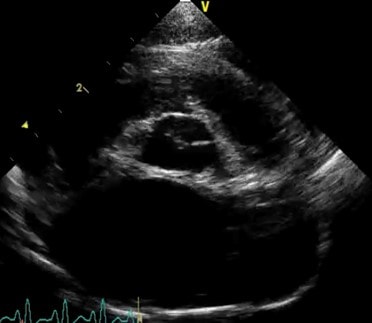

Ultrasound scan

Learning to perform a focused thoracic ultrasound scan or “TFAST” is extremely useful. This can be performed with the cat in sternal recumbency receiving oxygen therapy, and in cases of pleural effusion or obvious left atrial enlargement gives an immediate diagnosis for the

cause of dyspnoea:

| Black anechoic space surrounding the heart in a cat with pleural effusion |

Left atrial enlargement in a cat with acute CHF |

Lung ultrasound is an emerging technique which can help to differentiate between normal lung tissue, interstitial infiltration (such as oedema, pneumonia) and pneumothorax as well as identifying consolidation, masses or pyothorax/pleural effusion. The technique is best learnt with formal training and requires practice to be useful in reliable and repeatable rapid assessment of patients.